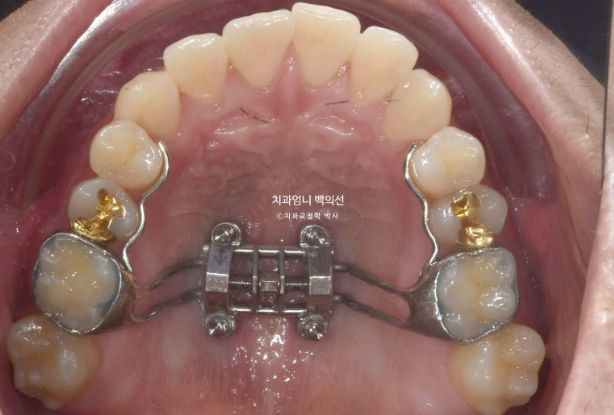

At our clinic, we use a palatal expansion device with miniscrews only for adults who truly need expansion of the palate.

After attempting arch expansion with an MSE palatal expander, we planned to resolve the open bite and crossbite with Invisalign.

First, we needed to expand the arch.

23.01

This is what it looked like in January 2023, one month after the initial visit, with the expansion device in place.

Expansion began in January 2023, and in February, although the suture had not yet opened, the expansion device could no longer turn. A minor procedure called corticopuncture was performed to actively promote separation of the palatal suture.

After that, expansion was successful in March, creating a large space between the front teeth.

After removing the parts attached to the teeth while leaving only the palatal section, we scanned, planned the treatment, and ordered the aligners.

We started wearing the first Invisalign aligners in July 2023.

The upper arch widened through the palatal expansion device